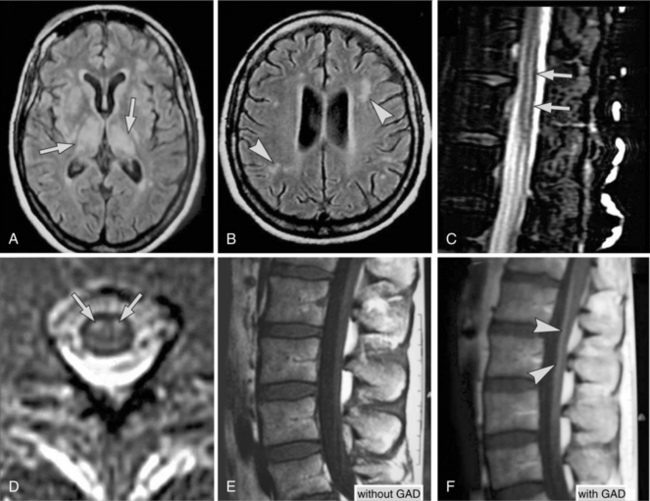

Differential diagnosis of the types of infections of the brain has improved with the use of MRI and PCR to diagnosis herpes simplex encephalitis. The electroencephalogram (EEG) will show seizure activity in the temporal lobe in herpes simplex. In general, lumbar puncture is abnormal with increased proteins. The glucose level, however, may be normal or moderately increased. CT scans do not show much until the damage is extensive. MRI shows cerebral edema and vascular damage earlier in the process and leads to earlier detection.1 In West Nile virus, lesions can sometimes be seen in the white matter, pons, substantia nigra, and thalamus. An important MRI finding is the focal abnormal signal intensity within the anterior horns; the level of abnormal spinal MRI findings corresponds to the paralysis. Change can be seen in the spinal roots, possibly a result of axonal degeneration secondary to spinal motor neuron loss or Wallerian degeneration in the spinal roots. Fig. 29-7 shows the imaging studies of individuals with West Nile virus.

Figure 29-7 Abnormal MRI findings in patients with West Nile virus. A, Image of the brain from a 57-year-old woman with encephalitis shows abnormal signals in bilateral thalamus and weighted MRI in other areas of basal ganglion. B, Focal white matter lesions are also seen. C, Sagittal T2-weighted MRI of the lumbar spinal cord shows abnormal signal intensity (arrows) conspicuous within the cord. D, Transverse view of the cord at the midlumbar level; abnormal signal intensity (arrows) is confined to the anterior horns. E, T1-weighted lumbar spine MRI from a patient with both meningitis and acute flaccid paralysis shows no discernible abnormality; however, after giving gadolinium contrast, spinal roots are significantly enhanced (F). (From Kramer LD: West Nile virus, Lancet Neurol 6(2):171-181, 2007; C and D from Li J, Loeb JA, Shy ME, et al: Asymmetric flaccid paralysis: a neuromuscular presentation of West Nile virus infection, Ann Neurol 53:703-710, 2003.)